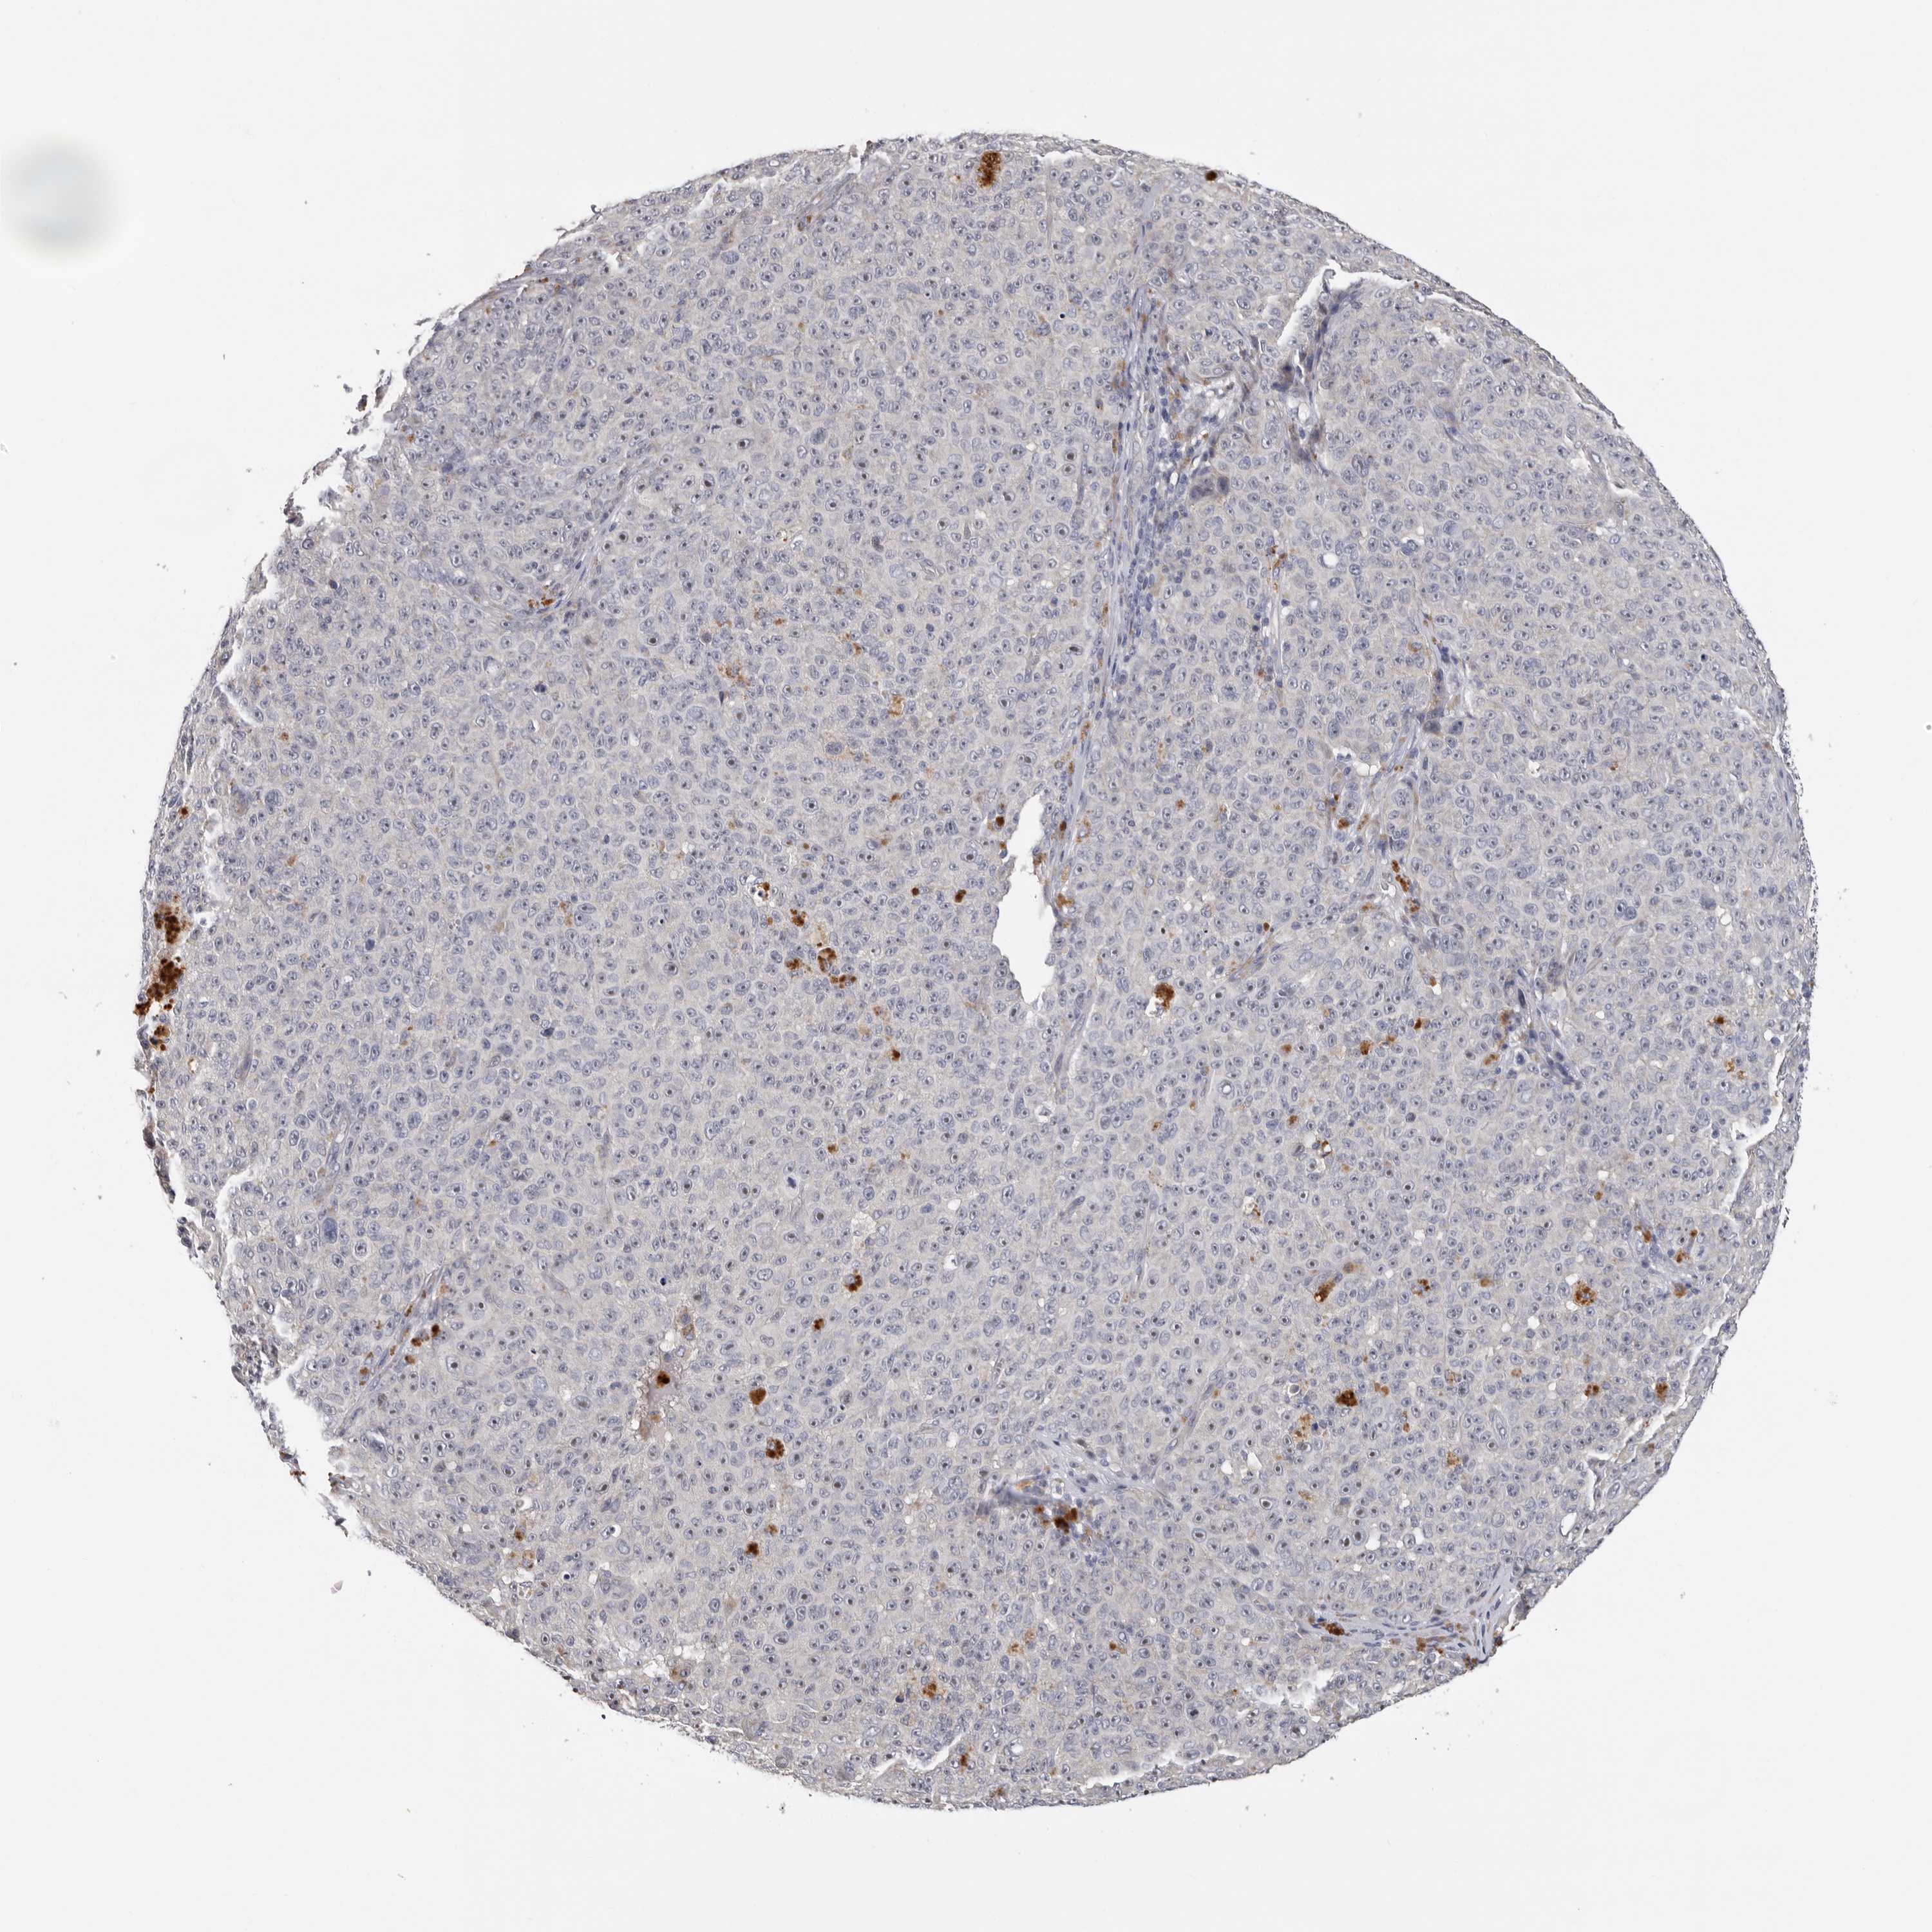

MELANOMA - Protein expressioni

A mouse-over function shows sample information and annotation data. Click on an image to view it in a full screen mode. Samples can be filtered based on level of antibody staining by selecting one or several of the following categories: high, medium, low and not detected. The assay and annotation is described here.

Note that samples used for immunohistochemistry by the Human Protein Atlas do not correspond to samples in the TCGA dataset.

Antibody stainingi

Antibody staining in the annotated cell types in the current human tissue is reported as not detected, low, medium, or high, based on conventional immunohistochemistry profiling in selected tissues. This score is based on the combination of the staining intensity and fraction of stained cells.

Each image is clickable and will lead to virtual microscopy that enables deeper exploration of all samples and also displays staining intensity scores, fraction scores and subcellular localization as well as patient and tissue information for each sample.

Antibody HPA023081

Antibody HPA023103

Antibody HPA024795

Staining

High

Medium

Low

Not detected

Intensity

Strong

Moderate

Weak

Negative

Quantity

>75%

75%-25%

<25%

None

Location

Nuclear

Cytoplasmic/membranous

Cytoplasmic/membranous,nuclear

Malignant melanoma, NOS

Malignant melanoma, Metastatic site